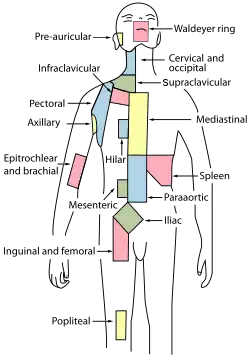

Regional lymph tissue

Regional lymph tissue Deep lymph nodes and vessels of the thorax and abdomen.

Deep lymph nodes and vessels of the thorax and abdomen.